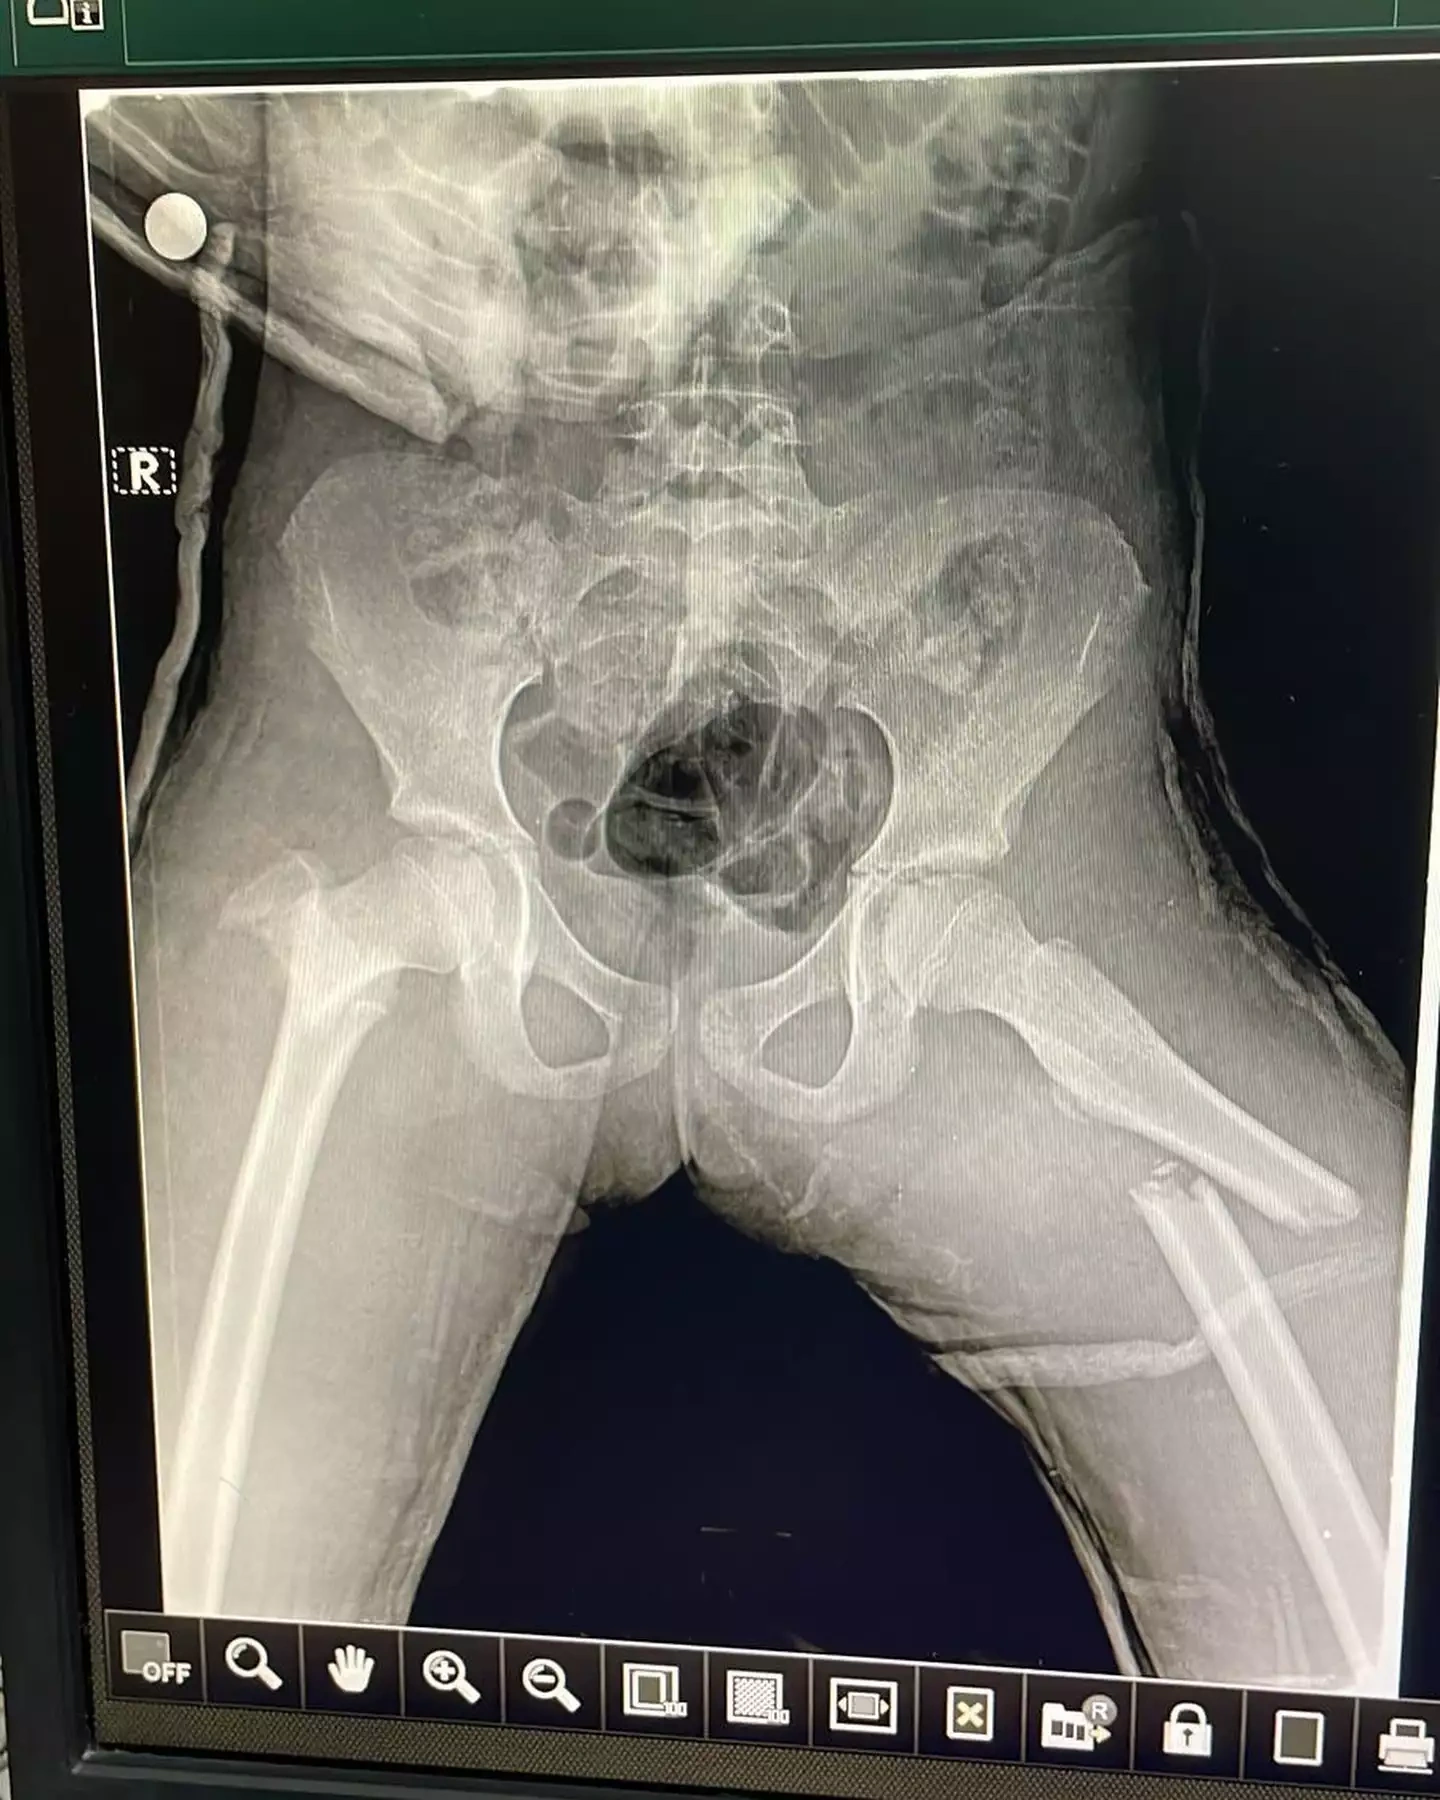

Hadisədən yalnız iki azyaşlı xilas ola bilib. Nərmin bildirib ki, onların da səhhətlərində ciddi problemlər yaranıb və maddi dəstəyə ehtiyacları var.